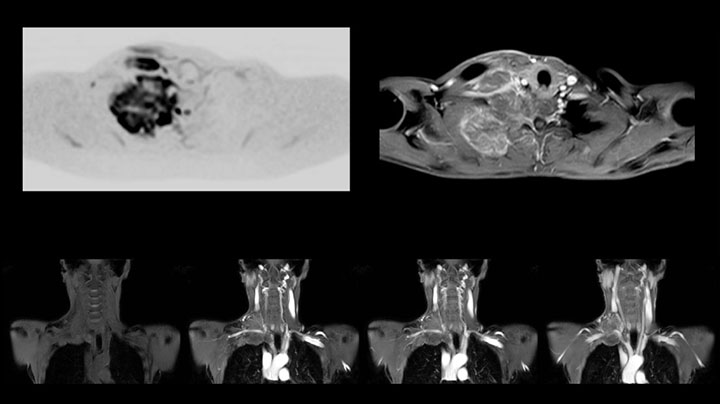

Die Prodiva Schulterspule ist sehr flexibel und hat eine große Abdeckung; dies erleichtert eine gute Positionierung, was wiederum zur ausgezeichneten Bildqualität und hohem SNR beiträgt, die wir in unseren Schulteruntersuchungen erreichen.

Scandauer: 2:55 Minuten, FOV: 160 mm, erfasste Voxel: 0,55 x 0,83 x 3,0 mm.

Scandauer: 04:19 Minuten, FOV: 160 mm, erfasste Voxel: 0,55 x 0,80 x 3,0 mm.

Scandauer: 02:50 Minuten, FOV: 160 mm, erfasste Voxel: 0,70 x 0,99 x 3,0 mm.